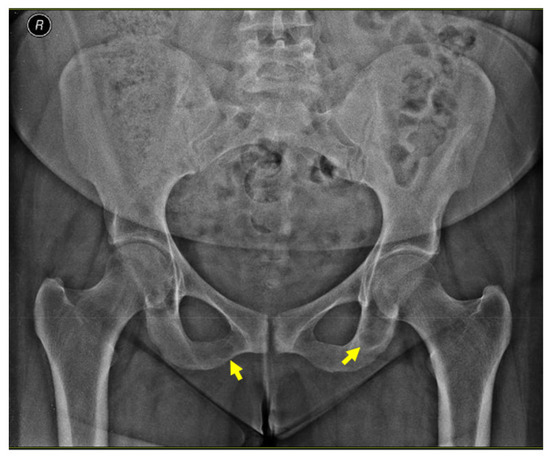

An X-ray of the pelvis also revealed multiple osteolytic lesions of the ischium (brown tumor features) with normal femoral head sphericity and position and a mildly reduced coxo-femoral joint space (Figure 4).

Figure 4.

X-ray of the pelvis: brown tumors at the level of the ischium (yellow arrows).